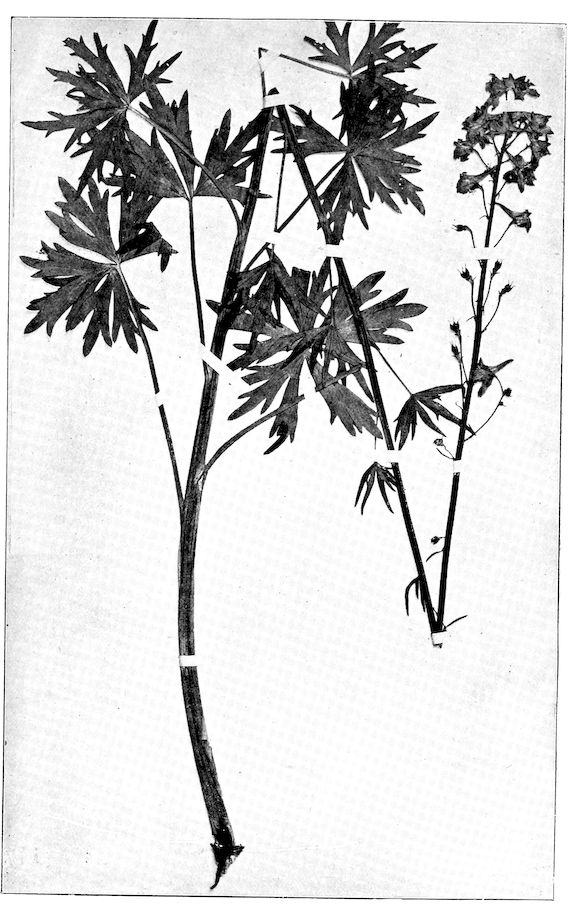

Fig. 1.—Rachitis in a young goat.